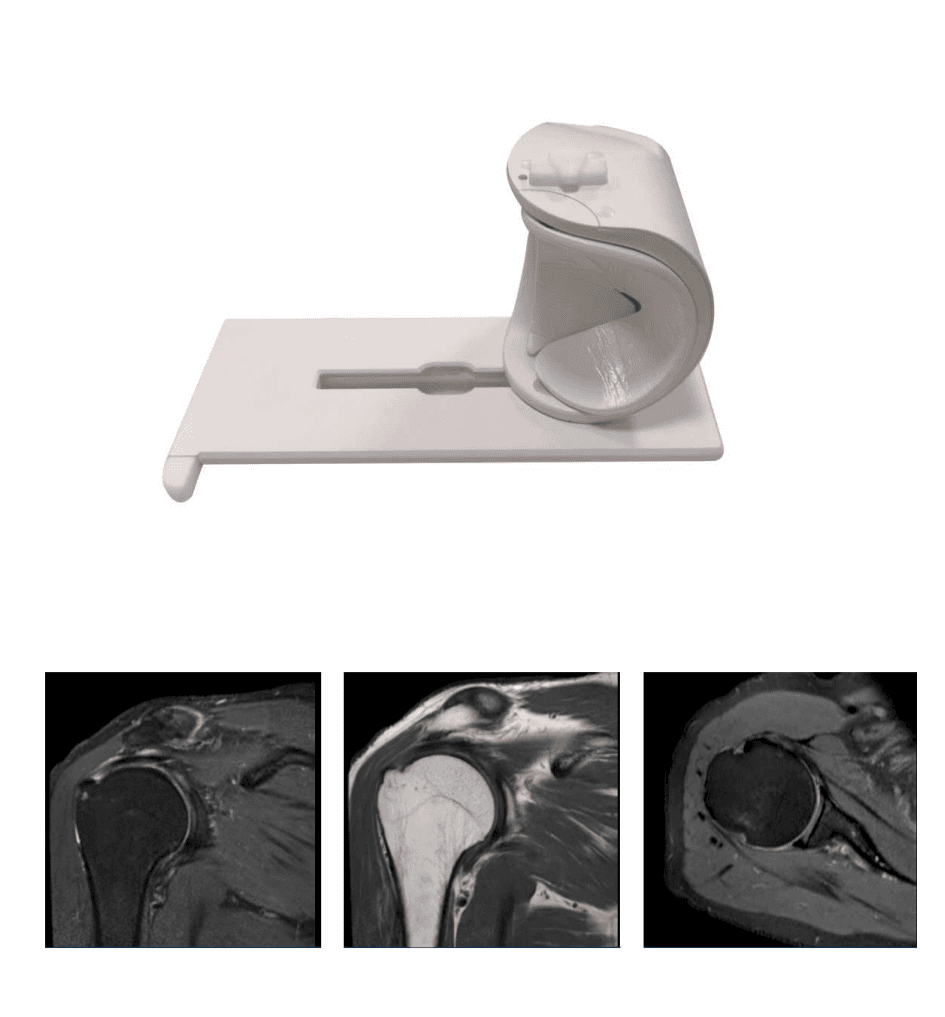

各种医疗床板定制(含碳纤维):适用于胃肠机,DR,dsa导管床等等...

Model: 床板定制